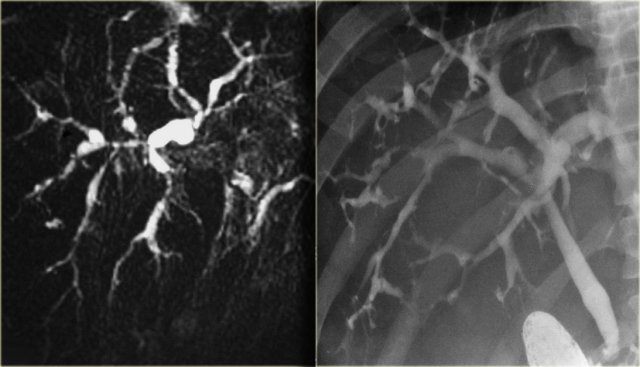

On the left a MRCP in a pateint with PSC.

Notice the large stricture, which is quite worriesome for cholagiocarcinoma (arrow).

The strictures in PSC show an abrupt transission, while here we see 'shouldering', which indicates mass-efect.

In addition there is intrahepatic dilatation proximal to this stenotic area.

On the left a MRCP in a patient demonstrating a stricture at the level of the hilum.

On MRCP this stricture looked long and worriesome for cholangiocarcinoma.

However, on the ERCP, the ducts have been distended with contrast and we can see that this is a short stricture compatible with the diagnosis of PSC.

During follow up this proved to be just PSC.